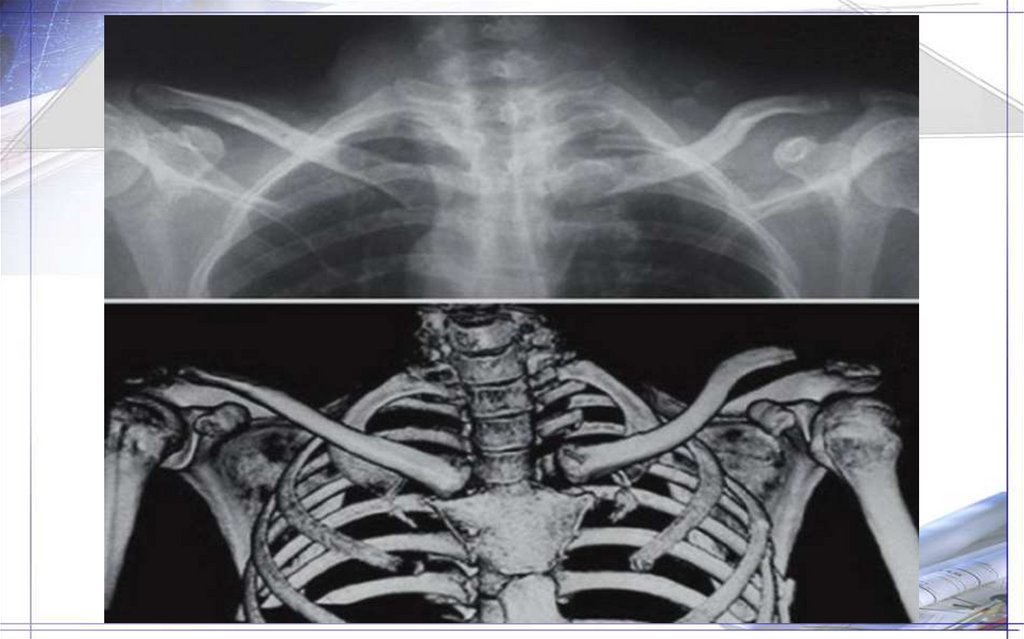

36. Плечевая кость(Humtrus)

37.

38.

39.

40.

41.

42.

43.

44.

45.

46.